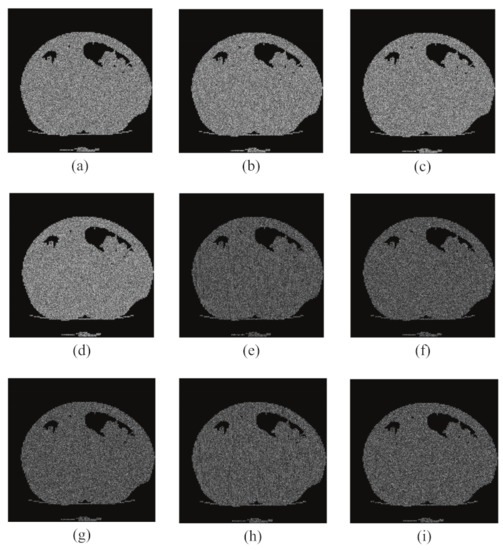

6.1. Simulation Results

6.3. Key Sensitivity Analysis